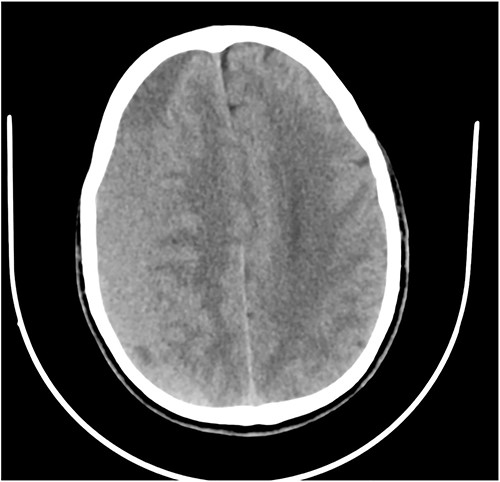

Case 3 – left isolated foot drop

A 78-year-old man with a 1-week history of headaches and dragging of the left foot. He had fallen in the bathroom 6 weeks prior to presentation. He had no other symptoms. Examination was unremarkable except for a left-sided foot drop with increased ankle jerk reflex. Brain CT done revealed a right-sided fronto-parieto-temporal CSDH (Figs 3 and 4). He had burr hole drainage and was discharged 3 days later to continue physiotherapy at home. At 4 weeks follow-up, his symptoms had completely resolved.